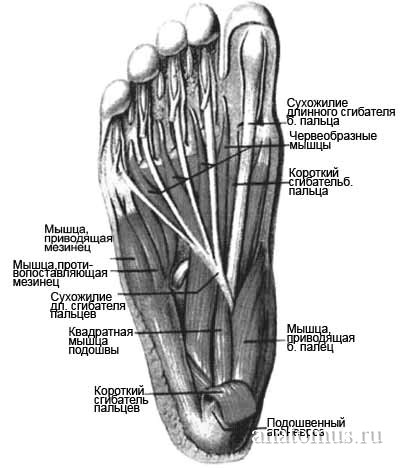

Анатомия подошвенной мышцы голени: подробное рассмотрение